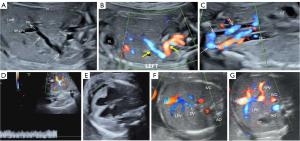

Type C: PV draining into iliac vein

Case 5: A 26-year-old gravida at 24 weeks and 4 days of gestation underwent an ultrasound that revealed an anomalous vessel originated from the PV sinus, then tracking posteriorly and laterally to the left hepatic region, between the liver and the gastric bubble, and descending into the pelvic area to merge with the right internal iliac vein (RIIV) (Figure 5A-5C). The venous flow in the abnormal vessel was noted to have a PSV of 21.2 cm/s (Figure 5D). The fetal heart was observed to be mildly enlarged (Figure 5E), and the DV, along with branches of the intrahepatic PV, were visualized (Figure 5F,5G), whereas the SV and the MPV were indistinct.

The pregnancy was terminated. Fetal autopsy findings revealed that the anomalous vessel, originating from the PV sinus (Figure 6A), measured approximately 2–3 mm in diameter, and descended to the left of the gastric bubble into the pelvis. It crossed the rectum and the left external iliac vessels before terminating in a connecting branch that entered the RIIV (see Figure 6B, in which the yellow arrow marks the connecting branch). This branch also extended to anastomose with the rectal venous plexus, and the RIIV was markedly dilated in comparison to the left internal iliac vein (Figure 6C). The infant showed oligodactyly with only four toes on each foot, along with syndactyly affecting some fingers and toes on the left hand and both feet. There was also partial agenesis of terminal phalanges in certain fingers and toes (Figure 6D).